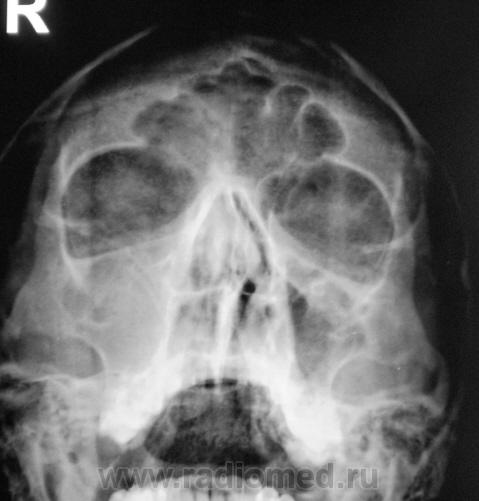

Пол пациента: Мужской пол Тип патологии: Другое Область исследования: Челюстно-лицевая область и шея Методы исследования: Rg Пациент направлен на рентгенографию придаточных полостей носа. Ваше мнение? https://radiomed.ru/sites/default/files/styles/case_slider_image/public/user/12/2..p8170059a.jpg?itok=7t4Nbh2k https://radiomed.ru/sites/default/files/styles/case_slider_image/public/user/12/3..p8170060.jpg?itok=IP4zEUbV https://radiomed.ru/sites/default/files/styles/case_slider_image/public/user/12/4..p8170060a.jpg?itok=H9fhfdKZ ID:5520 Ср, 18/08/2010 - 14:56 #1 Vikkur Не на сайте Был на сайте: 4 года 7 месяцев назад Зарегистрирован: 24.09.2009 - 14:34 Публикации: 1749 Мне видиться гиперпластический риносинуит, искривление носовой перегородки. причем спава практически тотальное затемнение.. Виктор. Ср, 18/08/2010 - 16:31 #2 Катенёв Валенти... Не на сайте Был на сайте: 7 лет 2 недели назад Зарегистрирован: 22.03.2008 - 22:15 Публикации: 54876 А, что по поводу нижнего края правой орбиты? У меня, что-то возникали сомнения, в "дефектности" этого контура. Ср, 18/08/2010 - 16:48 #3 Vikkur Не на сайте Был на сайте: 4 года 7 месяцев назад Зарегистрирован: 24.09.2009 - 14:34 Публикации: 1749 А есть ЛТ, потому что, я к своему стыду не вижу... Виктор. Ср, 18/08/2010 - 17:17 #4 Катенёв Валенти... Не на сайте Был на сайте: 7 лет 2 недели назад Зарегистрирован: 22.03.2008 - 22:15 Публикации: 54876 Есть. Сейчас выставлю. Ср, 18/08/2010 - 17:19 #5 Катенёв Валенти... Не на сайте Был на сайте: 7 лет 2 недели назад Зарегистрирован: 22.03.2008 - 22:15 Публикации: 54876 1 срез. Приложения: Ср, 18/08/2010 - 17:23 #6 Катенёв Валенти... Не на сайте Был на сайте: 7 лет 2 недели назад Зарегистрирован: 22.03.2008 - 22:15 Публикации: 54876 2 срез. Приложения: Ср, 18/08/2010 - 22:32 #7 Юрич Не на сайте Был на сайте: 6 лет 5 месяцев назад Зарегистрирован: 17.01.2010 - 09:55 Публикации: 351 я не вижу четко стенок в.челюстной пазухи справа - атрфия от давления? может мукоцеле? Чт, 19/08/2010 - 10:24 #8 Vikkur Не на сайте Был на сайте: 4 года 7 месяцев назад Зарегистрирован: 24.09.2009 - 14:34 Публикации: 1749 ассиметрия есть.. Виктор.

Мне видиться гиперпластический риносинуит, искривление носовой перегородки. причем спава практически тотальное затемнение..

А, что по поводу нижнего края правой орбиты? У меня, что-то возникали сомнения, в "дефектности" этого контура.

я не вижу четко стенок в.челюстной пазухи справа - атрфия от давления? может мукоцеле?

ассиметрия есть..